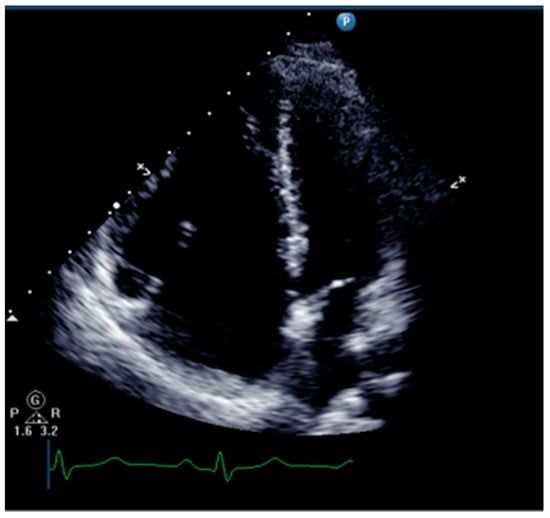

Right ventricular dilatation and paradoxical movement of the interventricular septum are common ultrasound signs of right ventricular dysfunction for qualitative assessment of RV (Figure 3). Physicians can measure the ratio of right ventricular to left ventricular end-diastolic volume in the apical four-chamber view. The RV/LV area ratio over 0.6 indicates right ventricular enlargement, while over 1.0 indicates severe enlargement [14].

Figure 3.

The ultrasound sign of right ventricular dilation.

Paradoxical movement of the ventricular septum is a sign of increased RV preload and afterload, especially afterload. The leftward shift of the interventricular septum can be observed in the short-axis view, causing the left ventricle to be compressed into a “D” shape [14]. It should be noted that not only chronic pulmonary hypertension can cause right ventricular dilation, but when pulmonary artery pressure suddenly increases, the right ventricle can also acutely enlarge.